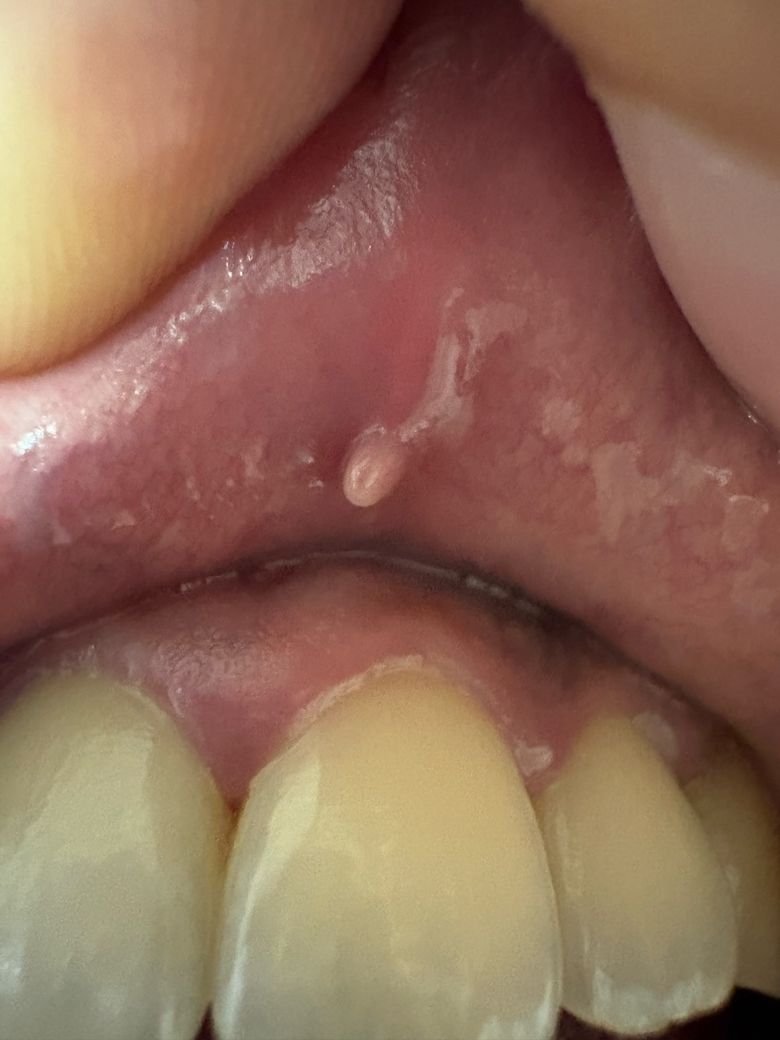

흡연은 7년반정도 해왔고 나이는 30입니다 상순소대끝쪽 윗입술 안쪽면에 물방울모양 하얀색 돌기가 생겼습니다 통증은없고 딱딱합니다 암일 확률이 있을까요?

악성병소의 양상은 아닙니다. 보통 악성종양은 경계가 불분명하여 생긴게 어지지하고 출혈이나 궤양등의 양상이 나타납니다.